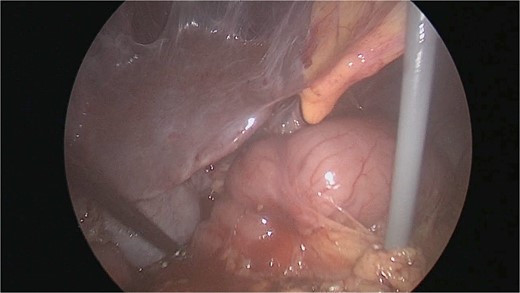

There were extensive perihepatic adhesions with involvement of the subhepatic space (Fig. 3). The initial intraoperative assessment was that this inflammation was secondary to a prior cholecystitis, but subsequent dissection revealed a pristine gallbladder (Fig. 4) with inflammatory adhesions in the pyloro-duodenal region (Fig. 5). All adhesions encasing the duodenum were lysed and the duodenum was kockerized (Fig. 6).

Extensive supra- and subhepatic adhesions were noted at laparoscopy.

The gallbladder was dissected free of the dense adhesions. There was no evidence of previous cholecystitis. The stomach (short arrow) was spared of adhesions, but the first and second parts of the duodenum were encased (long arrows).